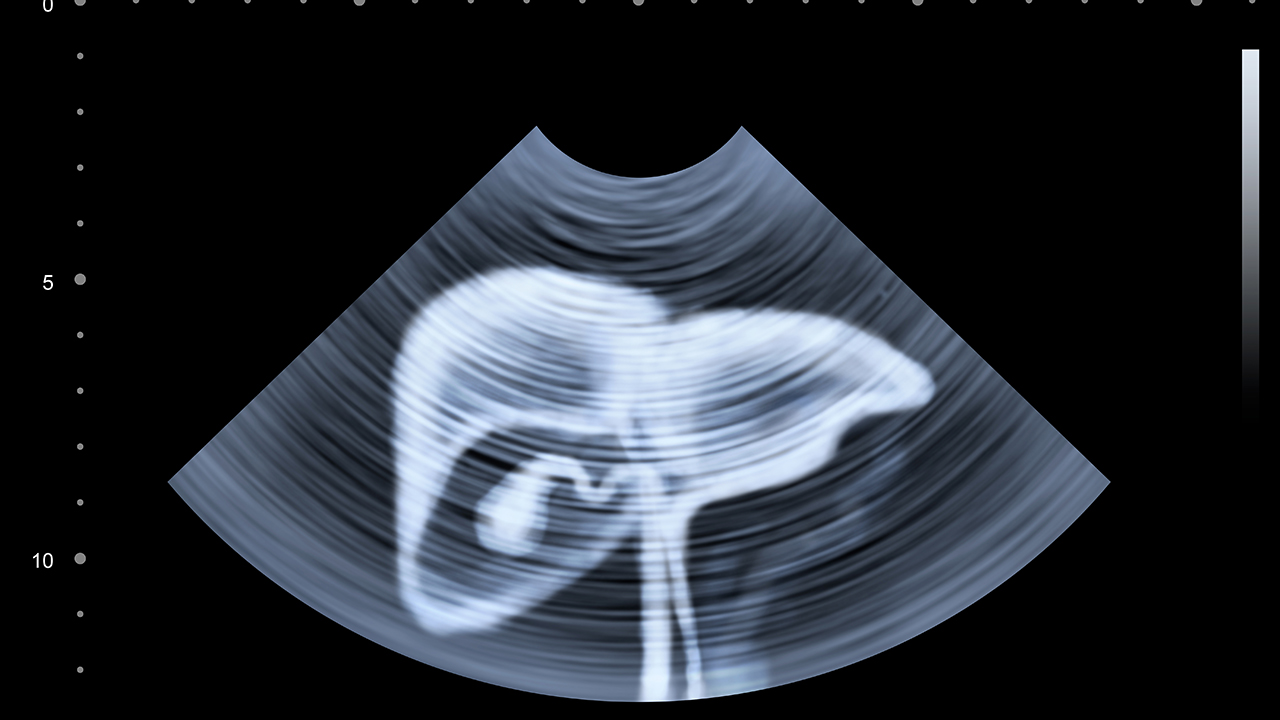

肝癌的预防与健康管理至关重要。对于高风险人群,如慢性乙肝、丙肝患者和肝硬化患者,应定期进行肝脏超声和甲胎蛋白检查。日常生活中应避免酗酒,注意饮食卫生,避免食用霉变食物。保持健康的生活方式,适量运动,控制体重,有助于降低肝癌风险。对于已确诊的肝癌患者,应积极配合治疗,定期复查,保持良好的心态,这对提高治果和生活质量都有积极意义。